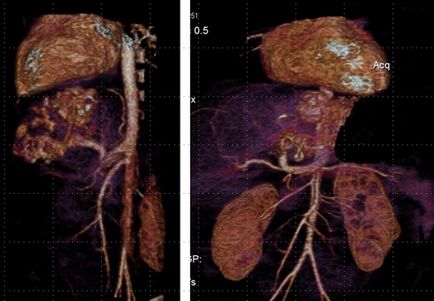

După 2 luni pe fondul tratamentului cu propranolol, structura educației sa schimbat, șuntul arterio-venos a dispărut între ramura arterei hepatice comune și cea inferioară a venei cava.

Caracter dinamic schimbare structurii neoplasmul sub forma reducerii diametrului vaselor de sânge și dispariția șunt arterio-venos, împotriva tratamentului conservator a ajutat confirma diagnosticul „congenital (infantil) ficat hemangiom.“

De asemenea, după dispariția șuntului arteriovenos, umplerea sângelui a organelor parenchimale sa îmbunătățit.